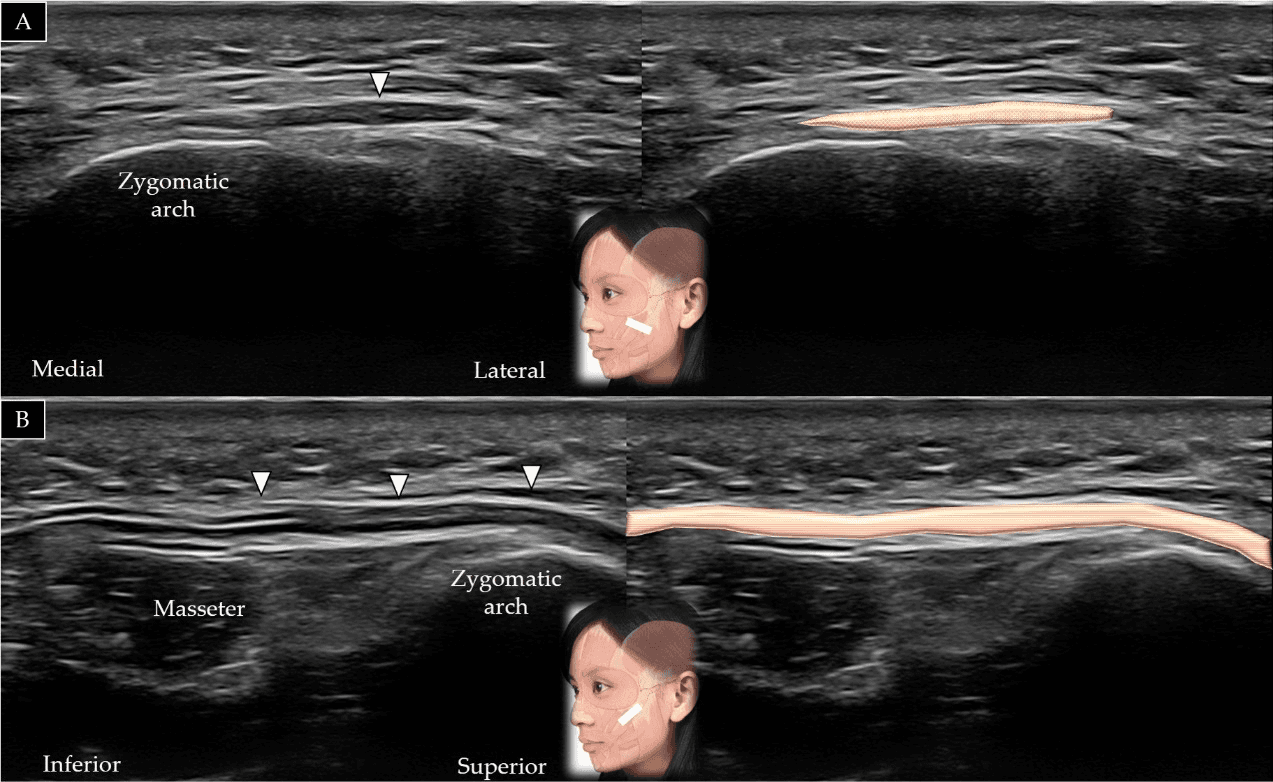

보툴리눔독소 - 교근(masseter)의 단축(A)과 장축(B)에 대한 초음파 스캔 및 도식적 표현입니다. 흰색 화살표와 회색 음영은 표재성 근건막계(super Figure 15. 교근(masseter)의 단축(A)과 장축(B)에 대한 초음파 스캔 및 도식적 표현입니다. 흰색 화살표와 회색 음영은 표재성 근건막계(superficial musculo-aponeurotic system), 검은색 화살표와 짙은 회색 음영은 이하선-교근근막(parotid-masseteric fascia), F와 노란색 음영은 지방(fat), 갈색 음영은 교근을 나타냅니다.